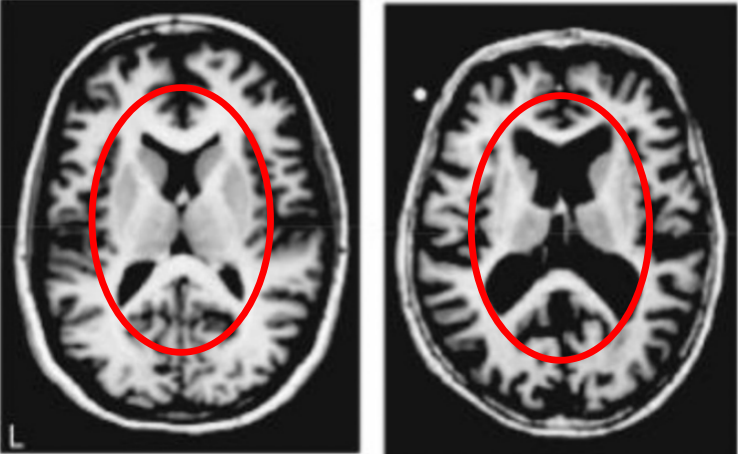

下图中有两张磁共振成像,左侧是年轻人的大脑,右侧是健康老人的大脑。从黑色面积的增加我们能清楚地看到脑组织的萎缩。

人类大脑的结构极为精妙,所以…也极为脆弱,脑萎缩几乎直接意味着多种认知功能受损。所以老年人经常会面对“记不住事”,“眼花耳背”,“手脚不灵便”这些问题。

但需要注意的是,右图中大脑的主人,已经94岁了。对于健康人来说,大脑的衰退…其实是个相当缓慢的过程。

现在我们换另一张图,这张图里的大脑看起来与刚才那张有着相似的萎缩,但它的主人其实是一个只有77岁,但患有阿尔茨海默症的老人。

即使大脑的萎缩和功能衰退不可避免,但阿尔茨海默症会大大加速这个过程。